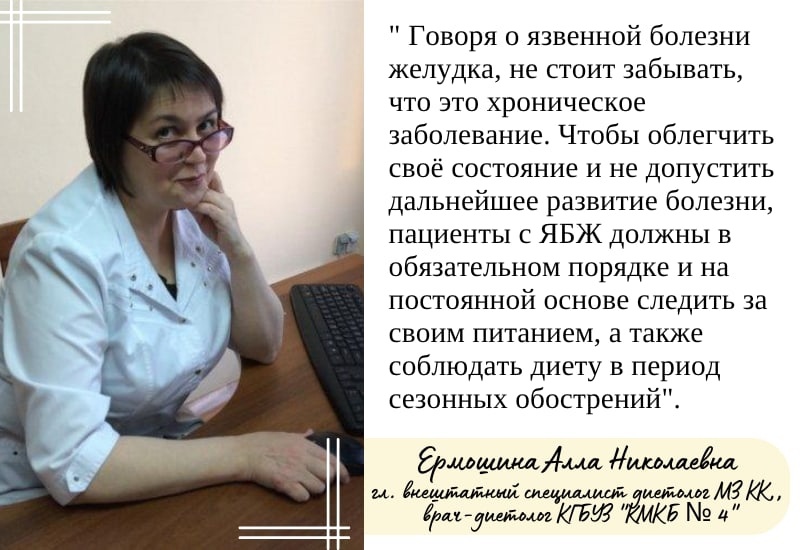

Рекомендации по питанию при язвенной болезни желудка

Язвенная болезнь желудка: факторы риска, симптомы и меры профилактики